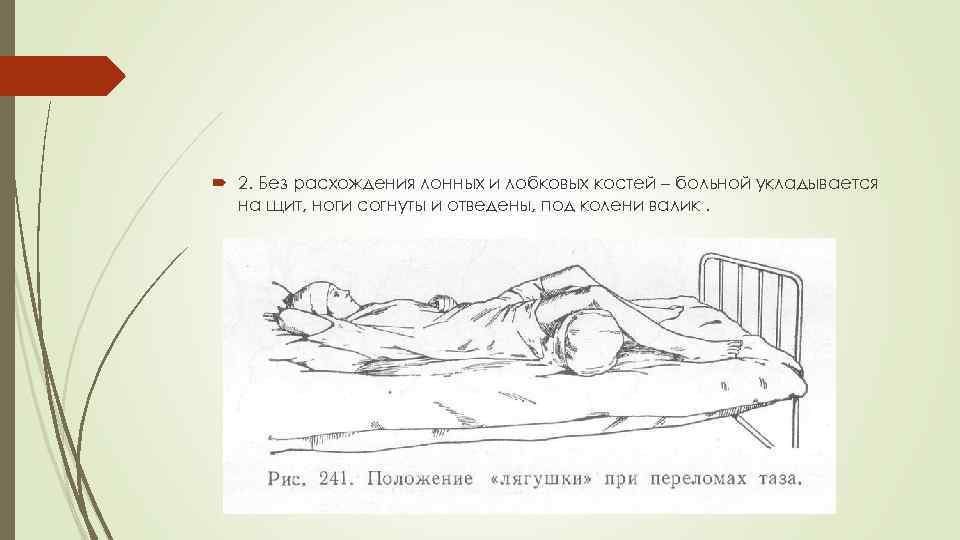

2. Без расхождения лонных и лобковых костей – больной укладывается на щит, ноги согнуты и отведены, под колени валик.